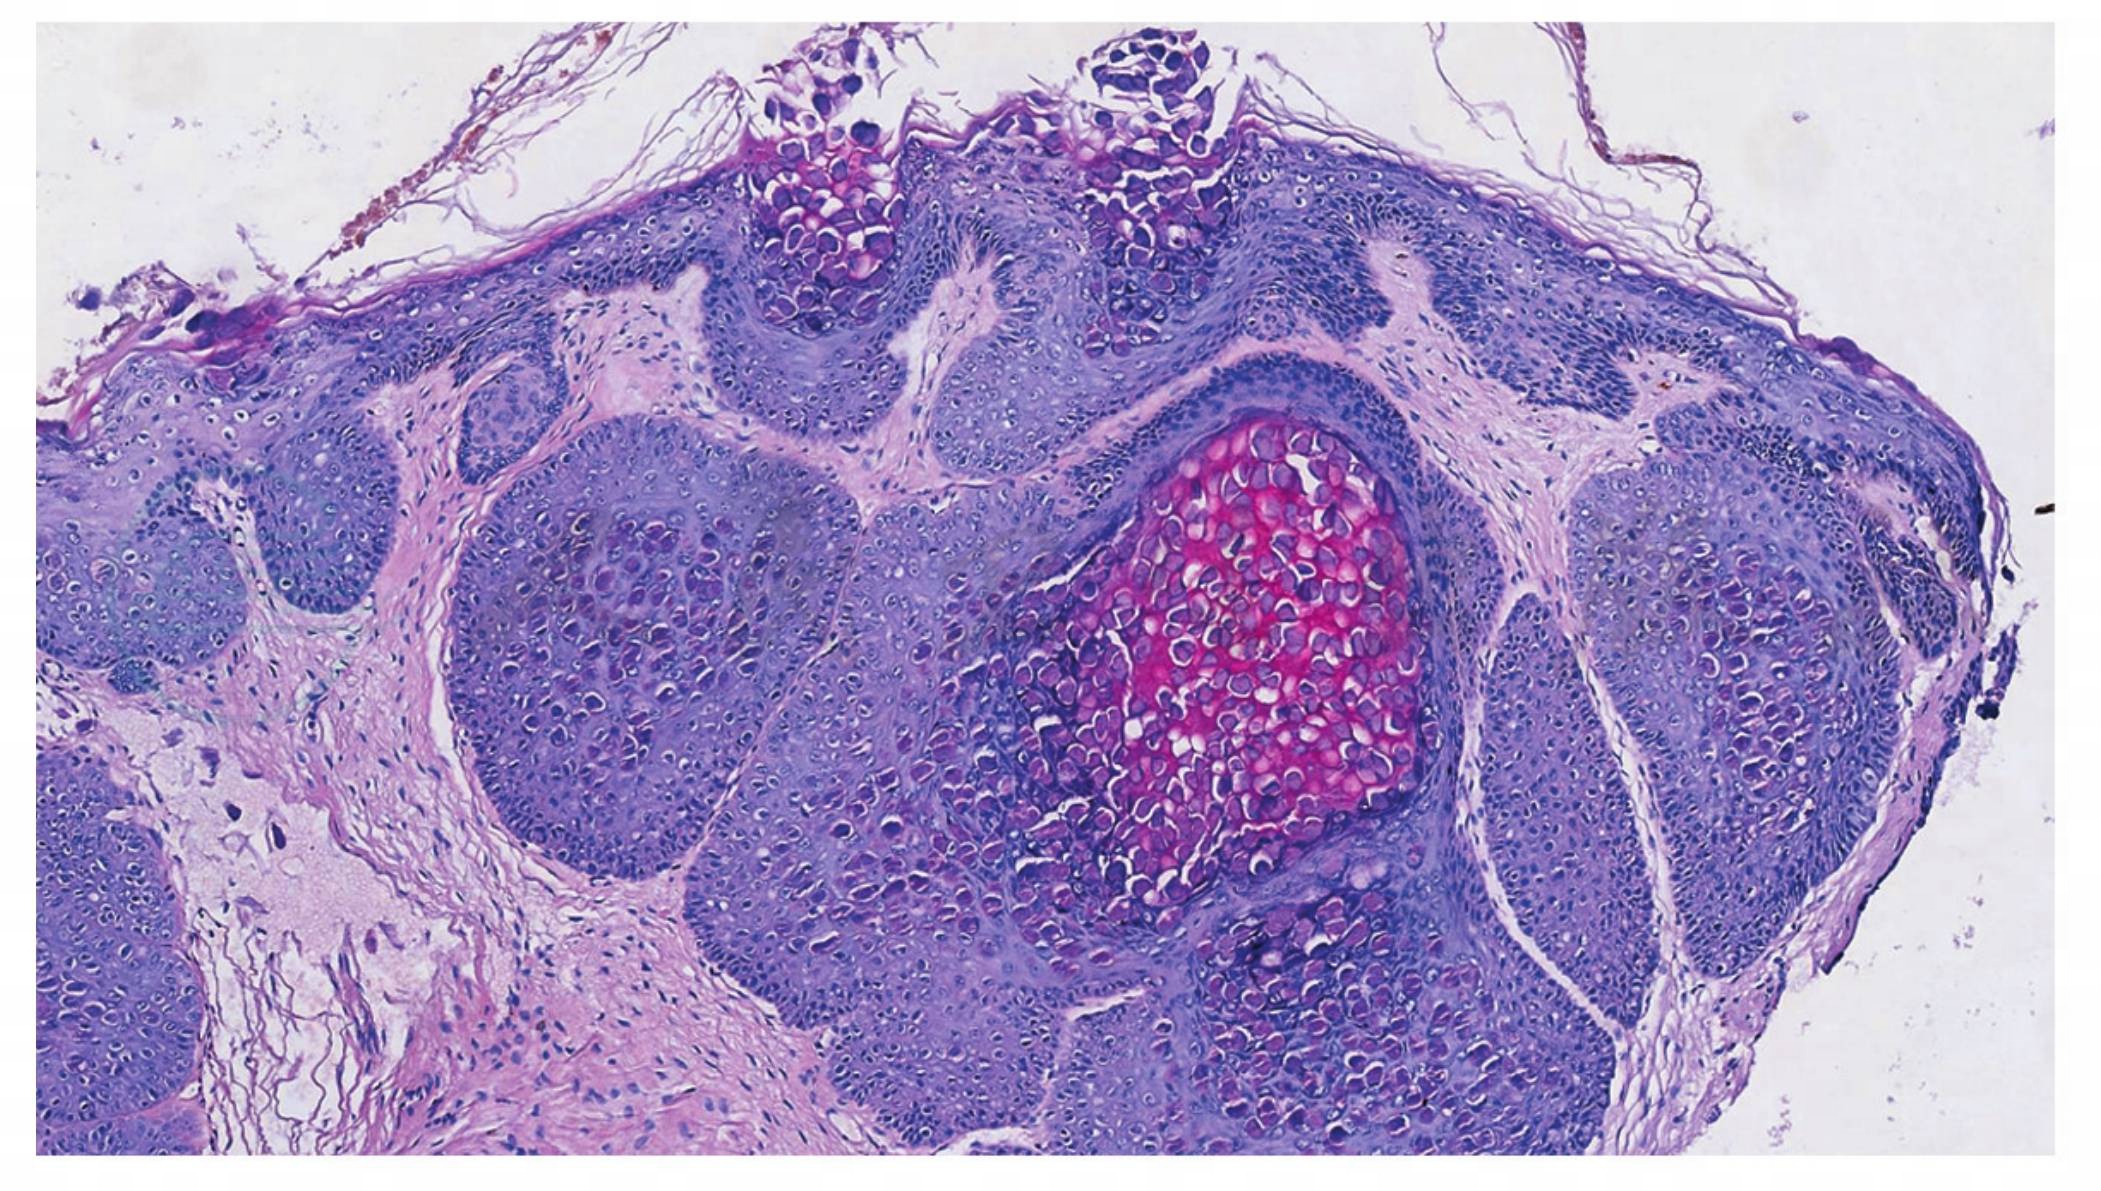

表皮角质细胞的胞质内有大的包涵体(软疣小体或Henderson⁃Patterson小体),随着它向皮肤表面移动,其体积逐渐增大(图1、图2)。

图1传染性软疣。棘层肥厚,其内大量嗜酸性包涵体(HE 染色,×100)

引自:协和皮肤临床病理学.第1版.ISBN:978-7-117-28737-1.主编:

特征性的是表皮细胞内出现多数细胞质内包涵体,称为软疣小体。其小体挤压每个受损细胞的细胞核,使胞核呈弯月状,位于细胞的边缘;软疣小体由嗜伊红变成嗜碱性,在角质层可见多数35μm直径大小的嗜碱性软疣小体,若中心的角质层破裂,排出软疣小体,形成有中心的火山口样。毛囊性传染性软疣,真皮内有多数扩大的毛囊,其中充满了软疣小体。